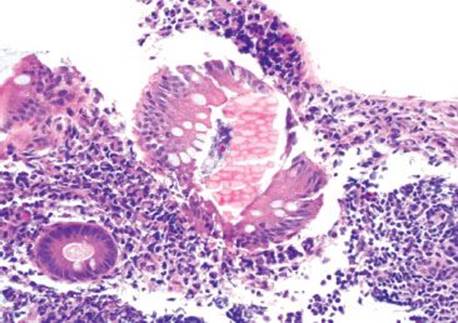

Figure 4.230 Melanosis coli. A variety of colorful entities can be seen in the colon. This is a striking example of melanosis coli, a finding linked to chronic laxative usage.

Melanosis coli refers to coarse, brown-black pigment in the cytoplasm of the colon’s resident macrophages. Despite the name, ultrastructural studies demonstrated the pigment is lipofuscin, not melanin (this particular factoid is a favorite among those who write test questions!).111 The pigment is derived from stimulant laxatives containing senna, aloe-emodin, chrysophanol, cascara, frangula, and rhein.112 The purgative effects of such preparations stem from their ability to increase colonic motility and decrease colonic absorption, resulting in decreased transit time and softer stools. The endoscopic images in patients with melanosis coli can be impressive (Fig. 4.231). Any region of the colon can be affected with no consistent regional pattern of involvement: some claim the distal colon is most affected, while others found the changes most pronounced proximally.113,114 Melanosis coli is seen in up to 73% of patients with chronic laxative usage and in up to 6% of biopsy and autopsy cases.115,116 Such findings have been documented within 4 months of regular laxative usage and the findings reverse 6 to 11 months following cessation (Figs. 4.232–4.238).117,118 Early literature suggested anthracoid laxatives were a risk factor for colonic neoplasia based on provocative animal and human studies showing an increased association of melanosis coli in patients with adenomas and carcinomas.119,120 Today, this theory has been abandoned.121,122